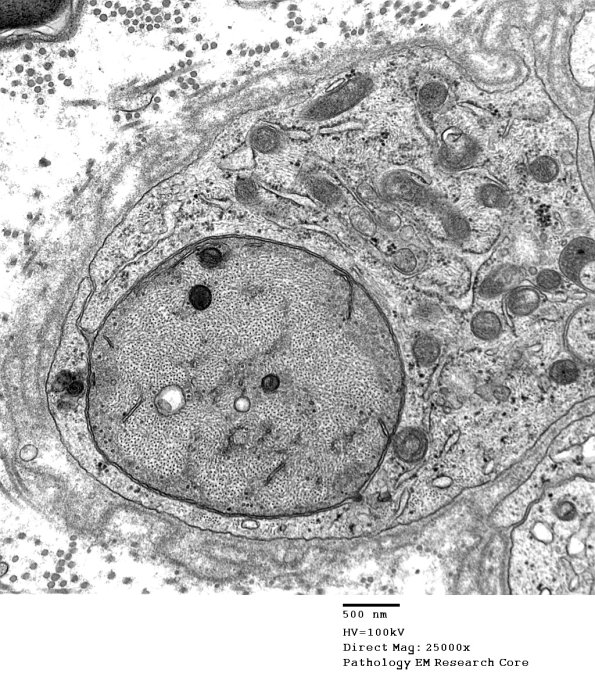

A photogenic demyelinated axon with prominent axonal cytoskeleton and reactive Schwann cell cytoplasm. (electron micrograph)